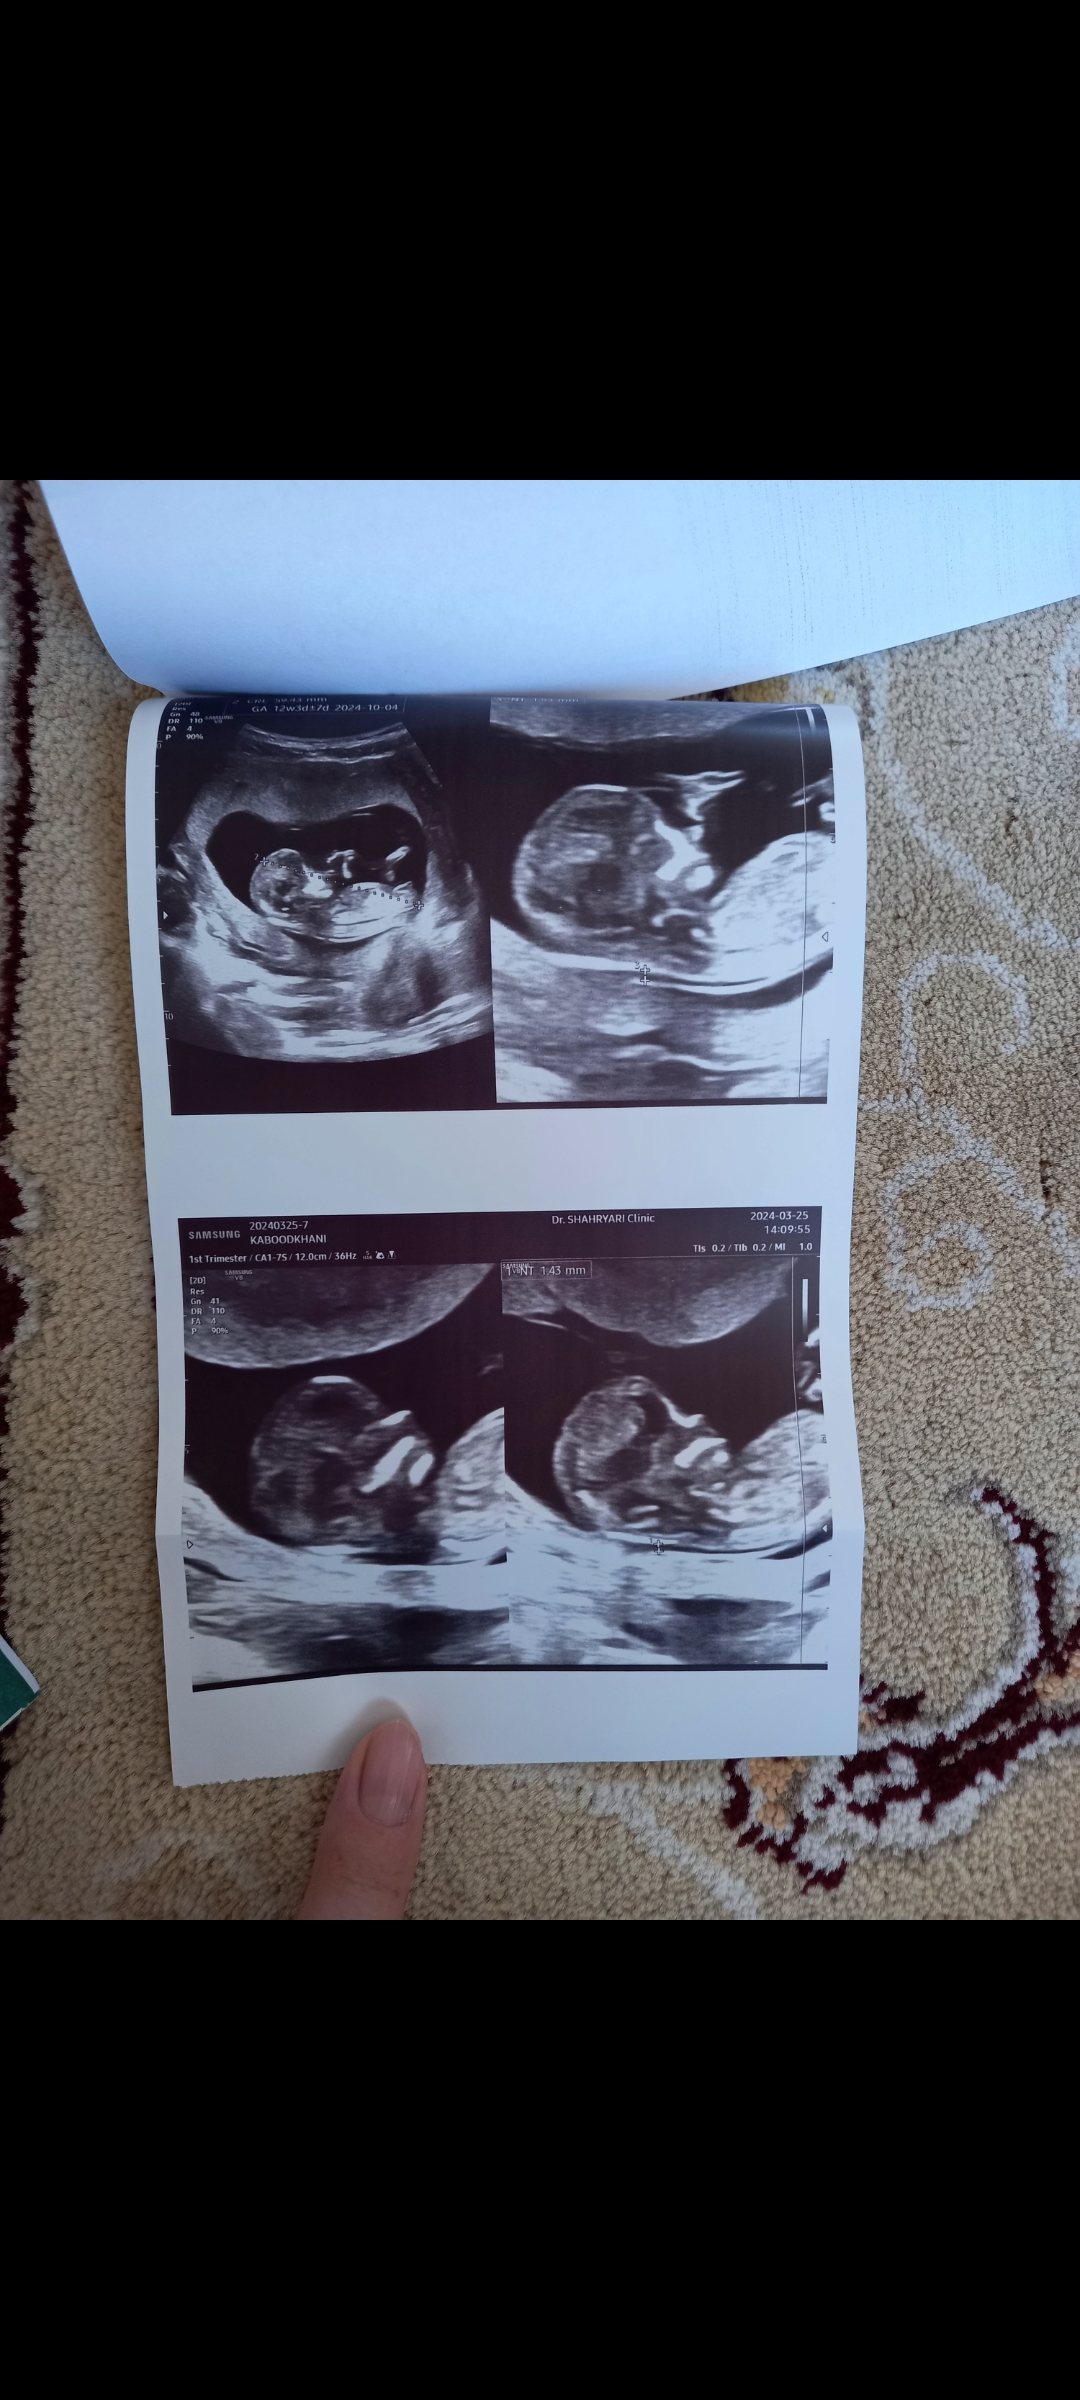

رفقا بیاین جنسیت نینی منو حدس بزنین عکسو اول میزارم

۱۲ هفته و ۳ روز رفته بودم گفته اخر ۱۴ هفته بیا برا جنسیت

الان ۱۳ هفته و دو روزم

ب نظرت بچم چیه؟

نمیدونم عزیزم بنظرم پسره چطور دکتر نفهمیده

گفت کوچیکه اخر ۱۴ هفته بیا برا جنسیت